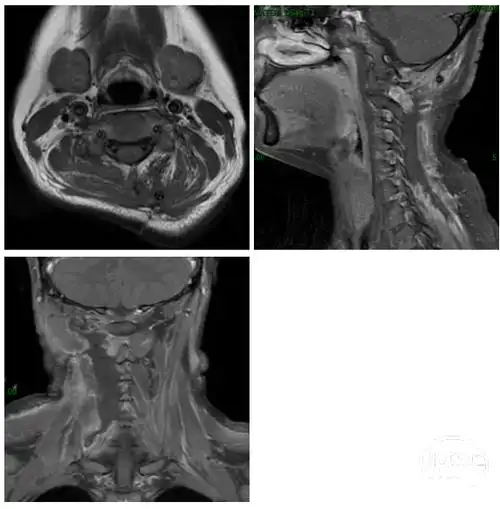

中国医学科学院肿瘤医院万经海教授头颈部韧带样纤维瘤一例